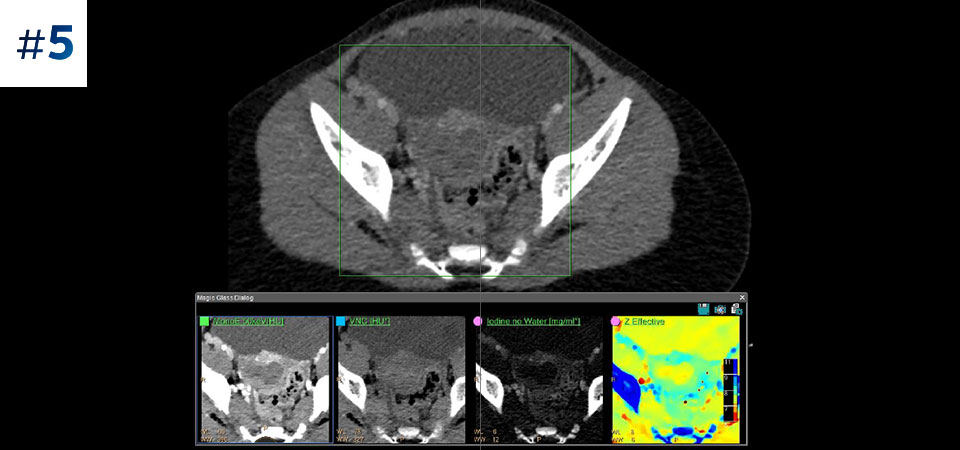

Reduced follow-up exams Improved tissue characterization and visualization may reduce the need for follow-up scanning for sub-optimal exams and incidental findings.